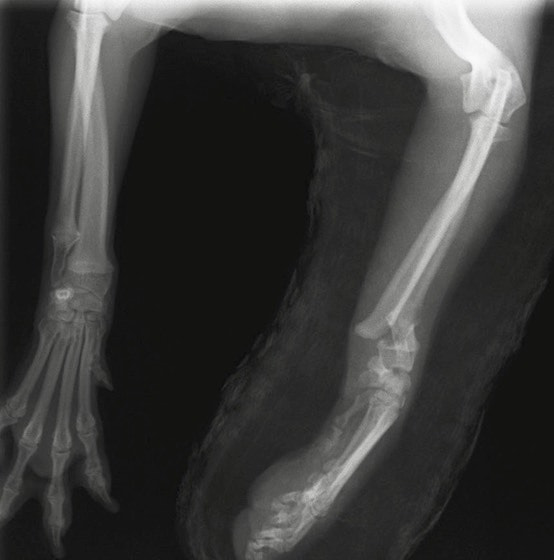

ペルシャ猫 11ヶ月齢 雄

他院にて左大腿骨遠位の成長板骨折(salter-harrisⅠ型)が認められており、治療相談を目的として来院。当院にて、キルシュナーワイヤーを用いたピンニングにより骨折部位の整復を行いました。術後の経過は良好で、現在も経過観察中です。

術後レントゲン